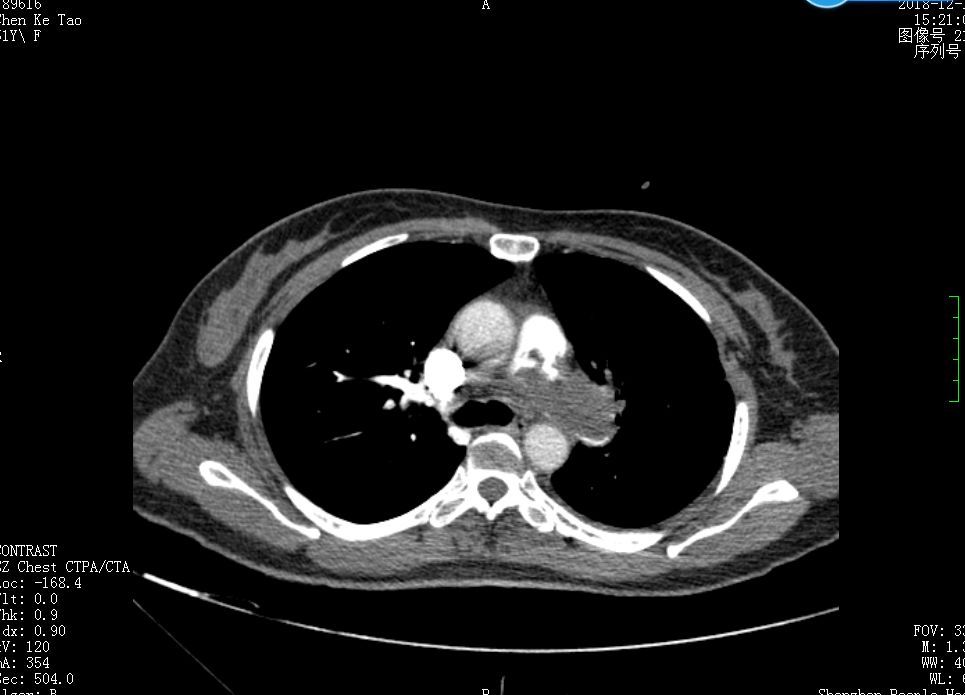

事件:深圳市人民医院首例肺动脉肿瘤摘除术+肺动脉内膜剥脱手术成功

2018年9月,51岁的陈女士(化名)无明显诱因出现咳嗽伴左侧胸痛,在当地医院就诊,被当诊断为为肺栓塞。

当地医院为陈女士行肺动脉造影术+肺动脉溶栓术,当时造影显示左陈女士右肺动脉主干见大量血栓,左肺动脉主干血栓几乎填满管腔!

然而,陈女士在外院经过多次介入下局部溶栓、抽栓治疗,效果却依然不理想。为了进一步治疗,陈女士转到了深圳市人民医院呼吸内科。

此时,陈女士已呼吸衰竭,重度肺动脉高压,随时面临猝死的危险。考虑到陈女士的病情,呼吸内科及时组织两次全院会诊,并联系多学科团队联合救治。

心外科郑奇军主任医师根据患者病史、辅助检查及诊疗经过,考虑陈女士可能是肺血管肿瘤,有手术指证,建议尽早在体外循环下行肺动脉肿瘤摘除术+肺动脉内膜剥脱术。

与家属充分交流后,决定在2018年12月8日上午安排急诊手术。

手术当日,陈女士过床后不久,出现呼吸急促、烦躁不安并突发意识丧失及循环障碍。心外科手术团队、麻醉师、手术护士立即协同抢救。

医护团队咬紧牙关、争分夺秒,成功为陈女士实行肺动脉肿瘤摘除术+肺动脉内膜剥脱术,切除的病变送病理检查,回报结果为肺动脉肉瘤!

幸好,术后的陈女士脱离了危险,恢复良好。